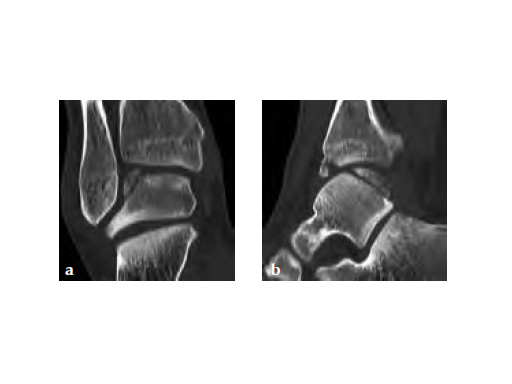

A 20-year-old construction worker fell from a 3 m height. He sustained a typical posterolateral impression and flake fracture of the talar dome.